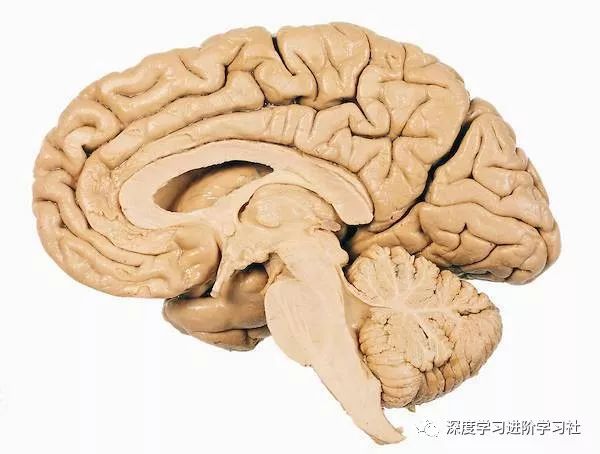

让我们使用半球横截面看看大脑的主要部分。因此,这是你脑袋里大脑的样子:

现在,让我们把大脑取出来,并删除左半球,这让我们能看清楚内部。

让我们来看看每个部分:

脑干及小脑(The Brain Stem and Cerebellum)

这是我们的大脑最古老的部分:

我们的大脑横截面中青蛙大脑的残留。事实上,青蛙的整个大脑与我们大脑的低水平部分相似。

当你了解这些部分的功能,它们很古老这件事就说得通了:一切这些部分能做的事情,青蛙和蜥蜴都可以做。以下是主要部分:

小脑(The cerebellum)

这个看起来像你大脑阴囊的东西是你的小脑,它使人保持平衡、协调和正常移动。

边缘系统(The limbic System)

皮层(Cortex)

最后,我们到达了大脑皮层。

大脑皮层(本文主要指新皮层,文中统称皮层)基本上负责所有事情:看,听,触觉,语言,动作,思维,规划和个性。